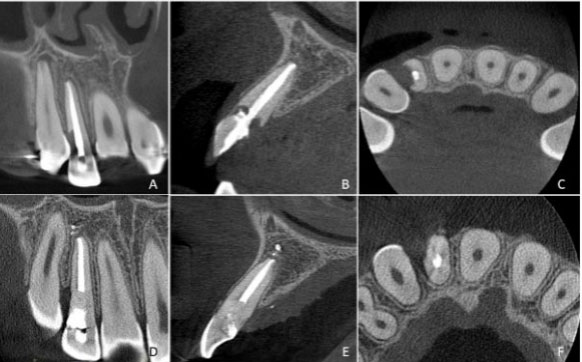

Tooth 12 was submitted to orthodontic traction with the aim of enabling the restoration, this treatment option was initially considered with the aim of not causing a gingival margin defect and preventing the percolation of salivary fluids into the root canal system. After 10 months of follow-up after orthodontic traction, radiographically showed an increase in the resorptive lesion (Figure 1B) and therefore, a cone beam computed tomography (CBCT) was requested for a multiplanar evaluation of the lesion (Figure 2). Cone beam computed tomography showed severe invasive cervical resorption, which extended apically and communicated with the endodontic filling material. In February 2020, a surgical intervention was performed to remove all the granulation tissue in the region of resorption and subsequent filling with bioceramic material (Biodentine—Maur-des-Fossés Cedex, França) (Figure 1C).

Figure 2: (A–C): Tomographic appearance of tooth 12 after 10 months of treatment showing an increase in the resorptive pocket. (D–F): Tomographic follow-up after 24 months.